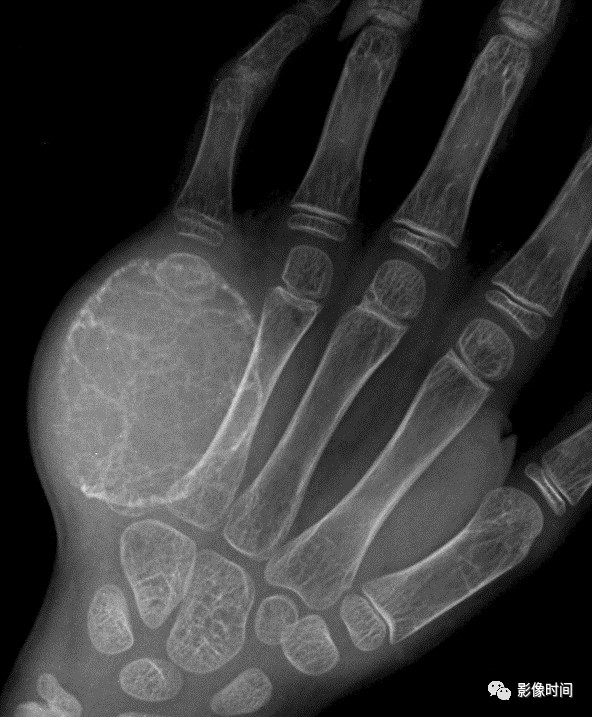

掌指骨常见肿瘤的影像学表现